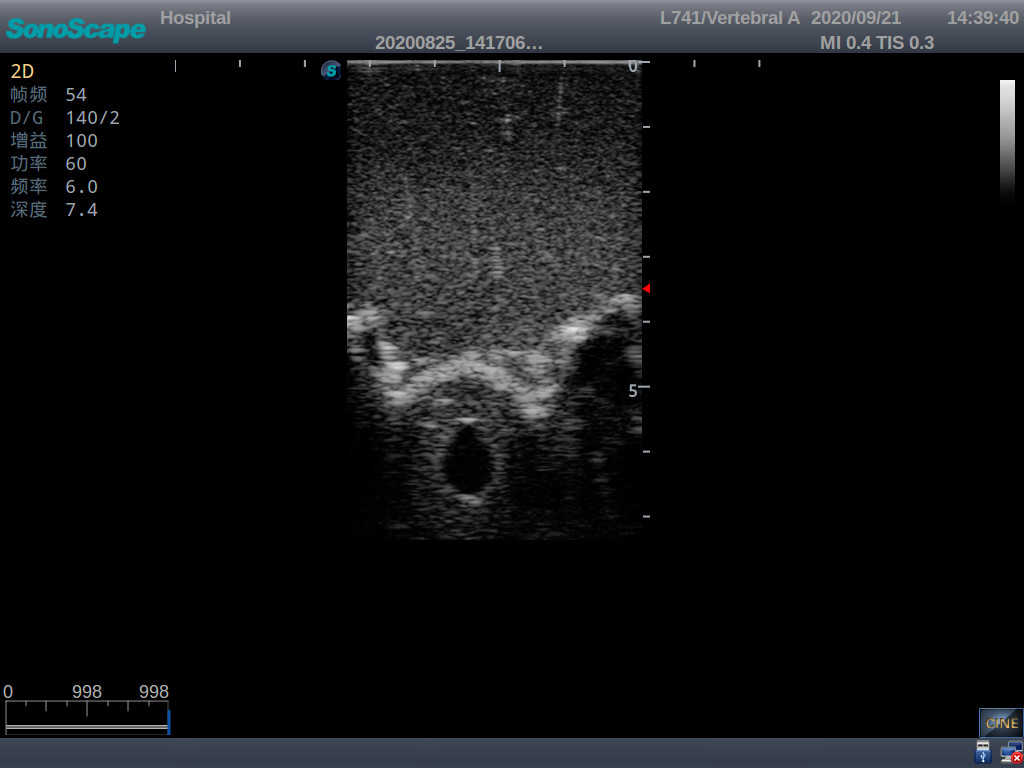

This model is an ideal choice for ultrasound-guided adult lumbar puncture training with true-to-life skin feel and touch, accurate anatomical structures as well as real clinical ultrasound images. Realistic resistance to needle tips and correct landmarks provide excellent hands-on experience.

2)  Real clinical ultrasound images

3)  Compatible with various real ultrasound machines

1)   Ultrasound-guided lumbar puncture practice